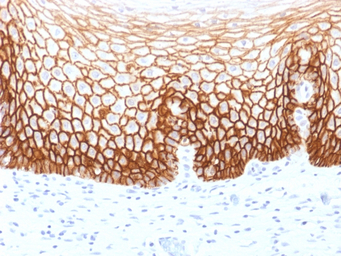

IHC-P analysis of human cervical carcinoma tissue using GTX34523 CD44v9 antibody [CD44v9/1459].

IHC-P analysis of human tongue carcinoma tissue using GTX34523 CD44v9 antibody [CD44v9/1459].

IHC-P analysis of human prostate carcinoma tissue using GTX34523 CD44v9 antibody [CD44v9/1459].